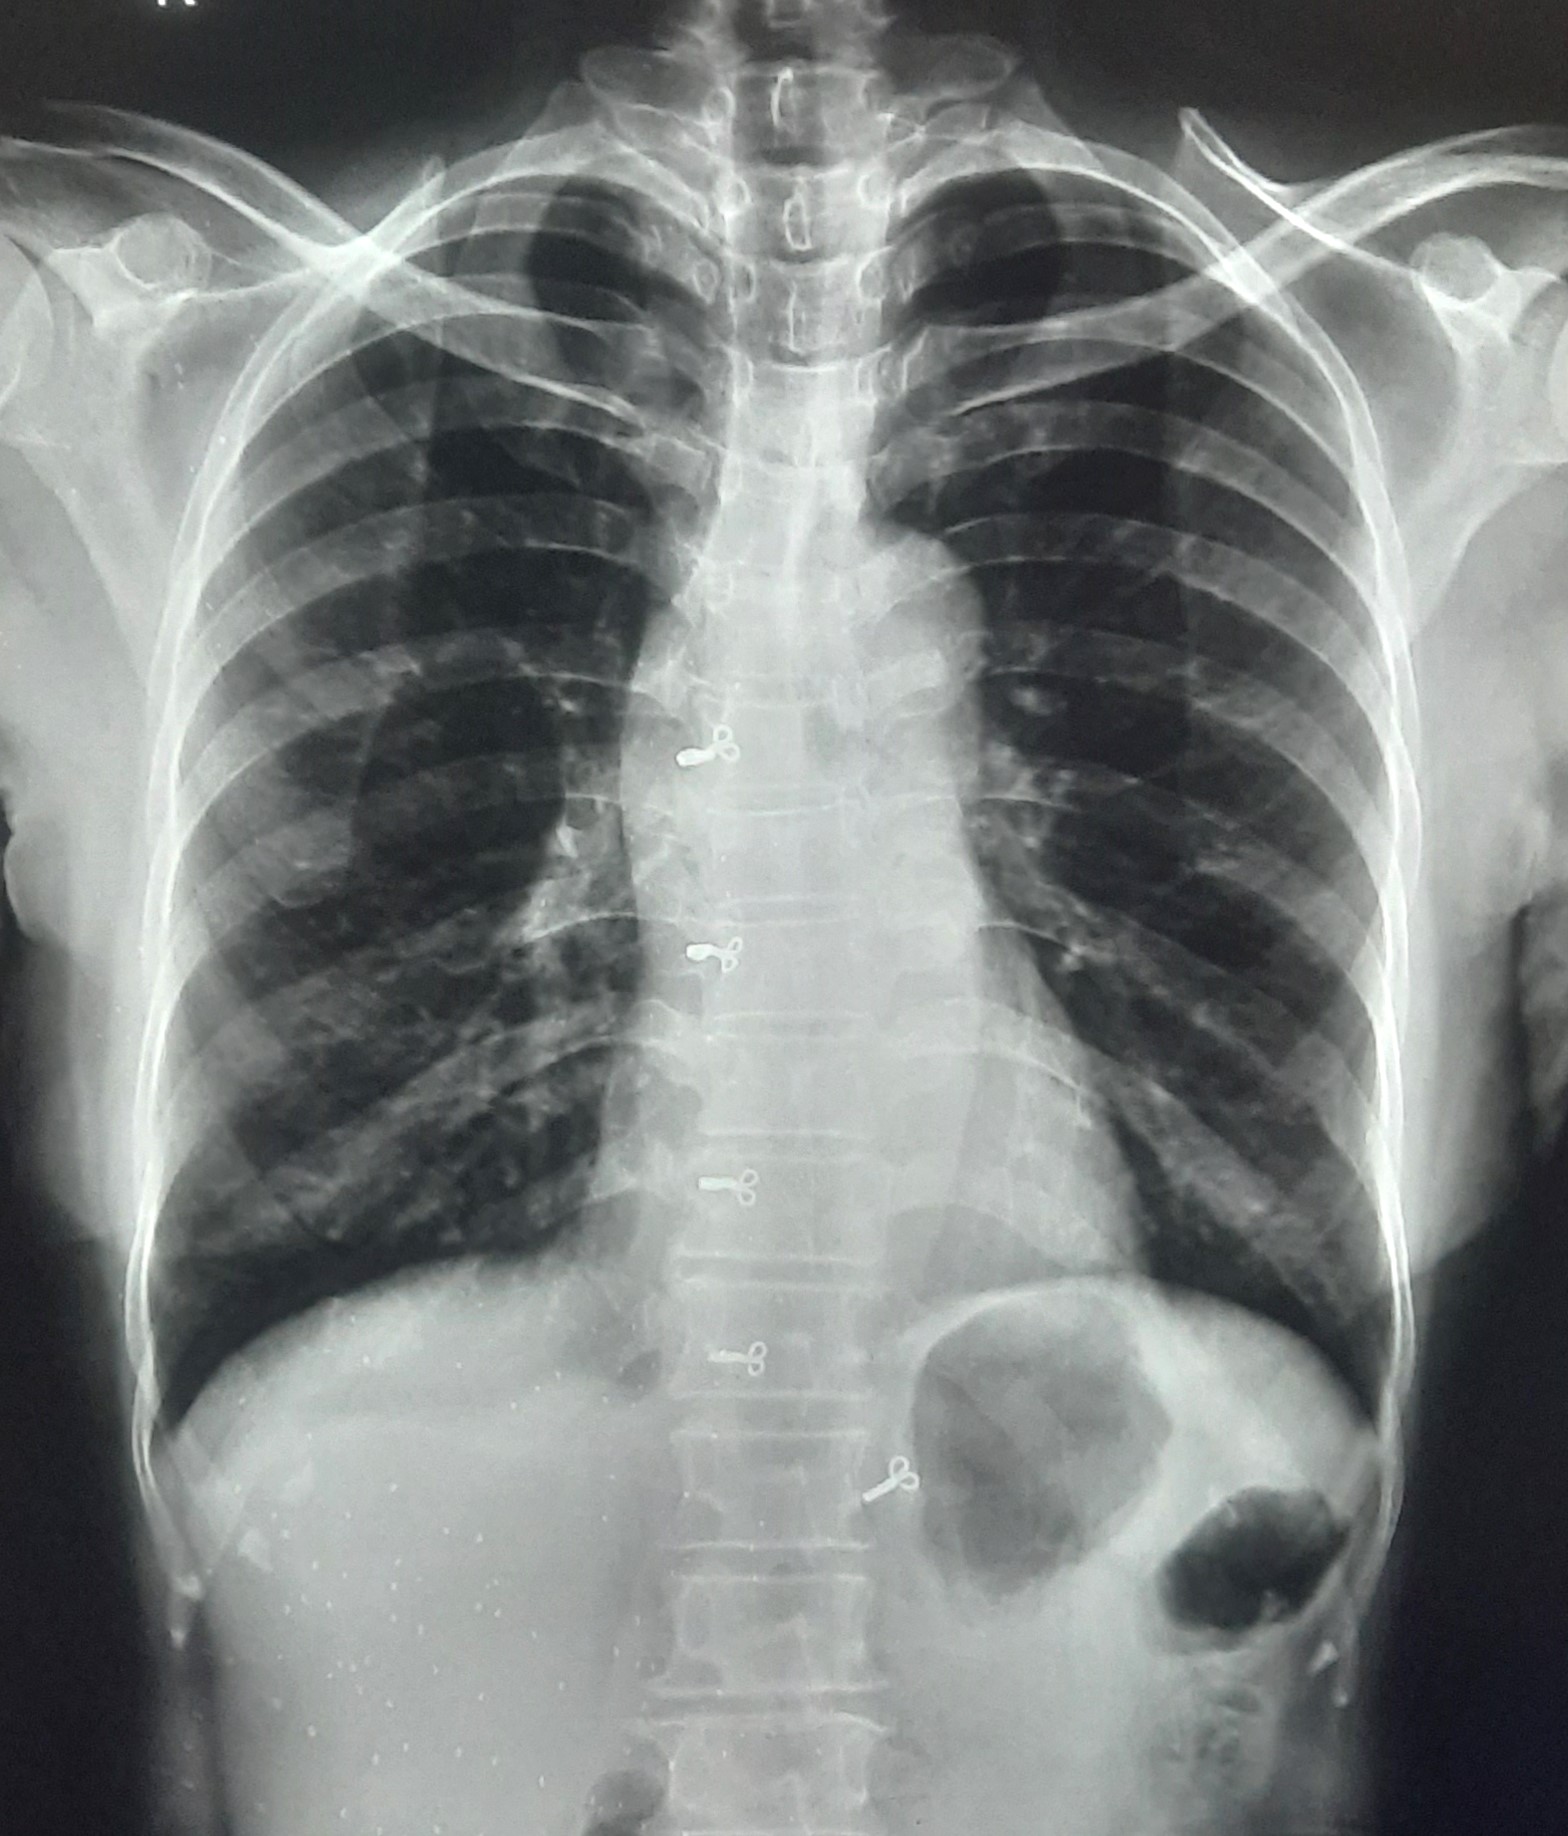

| 211 | IGGMC, Nagpur, Nagpur | P2 | 29-4261 | DHANRAJ HEDAU | Consent taken on Paper | 65 Yrs. |

Provisional Diag : Lung mass with ? Malignancy

Final Diag : Lt lung mass with malignancy (T1 N1 M1) with pneumothorax |

Result awaited (Suspected TB/Non-TB) | Abnormality visible on x-ray |